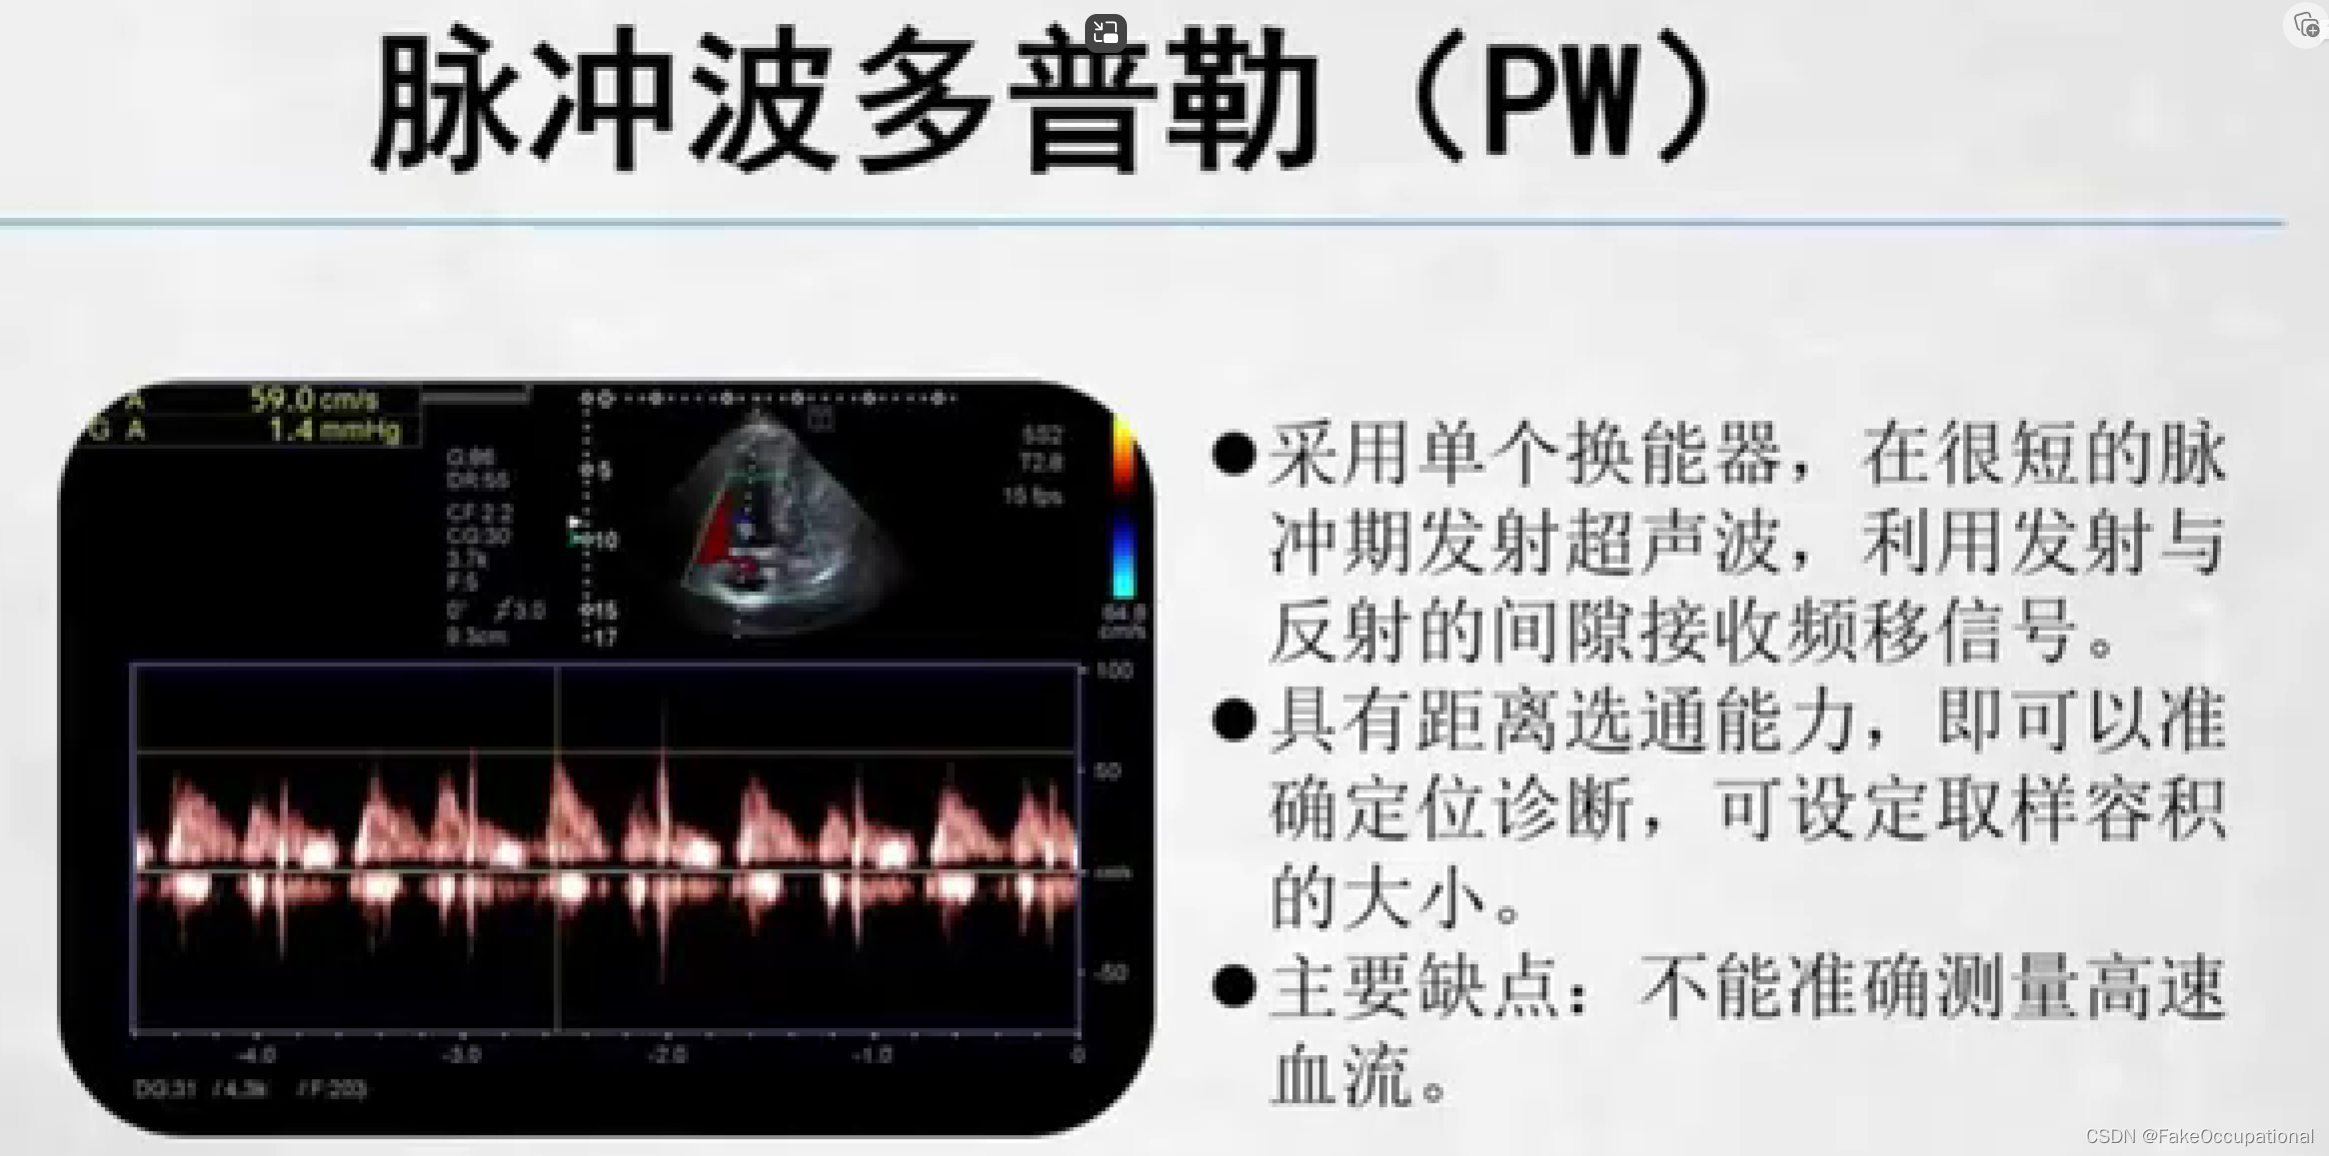

- 以频谱曲线显示,检测血流动力学参数:脉冲波多普勒(PW),连续波多普勒(CW),组织多普勒(TDI)